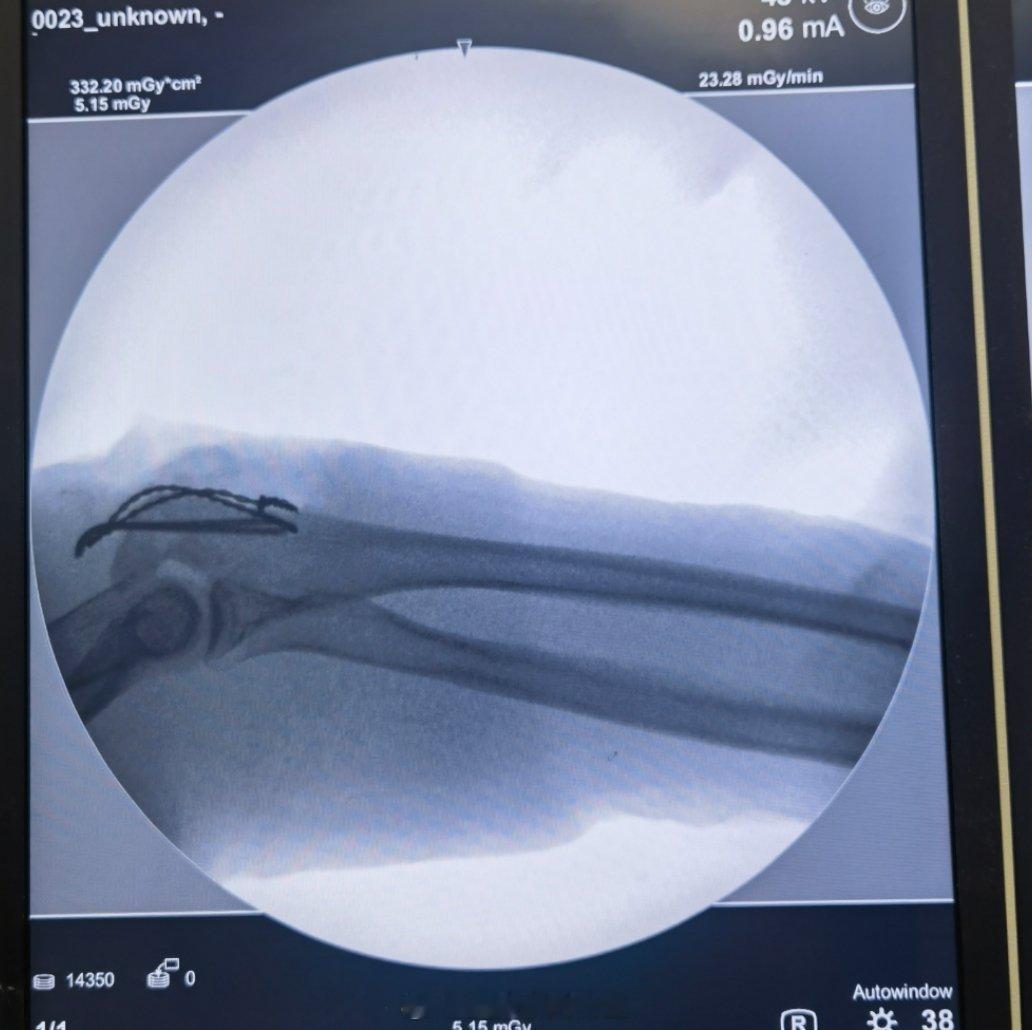

一年轻幼儿园老师,假期当伴娘摔倒,肘关节着地导致骨折,经呼吸同事介绍从济宁来济南找我,手术选择尺骨鹰嘴骨折切开复位张力带钢丝固定,最经典的一种手术方式,简简单单,经济实惠…